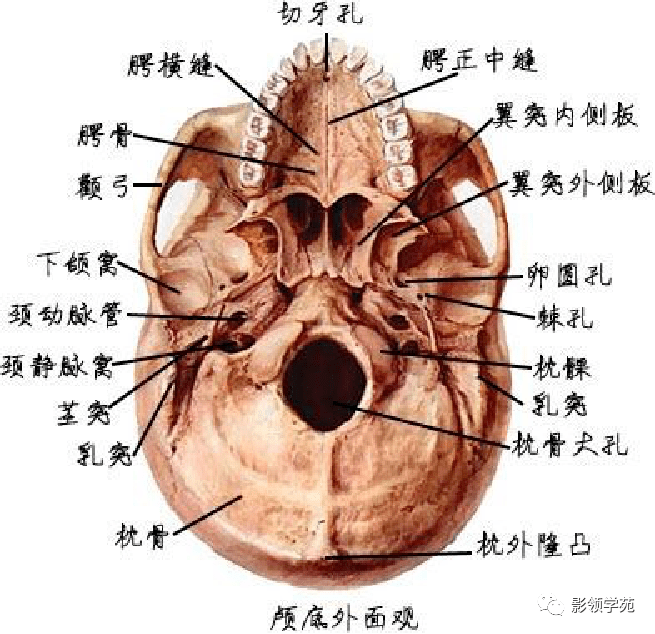

骨骼系统

骨骼系统